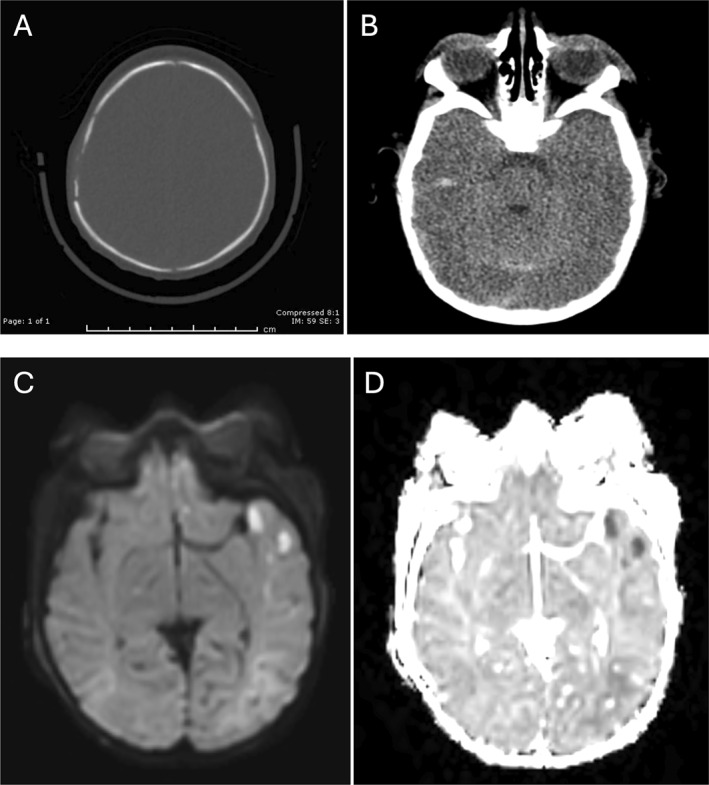

Abstract Image